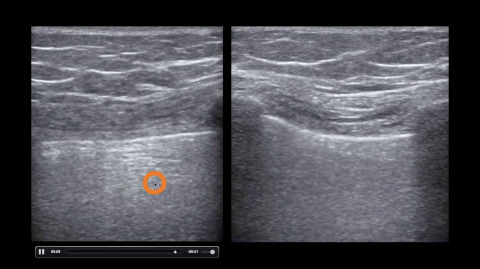

B-Lines

Jacob Avila explains the difference between A-lines and B-lines on lung ultrasound.